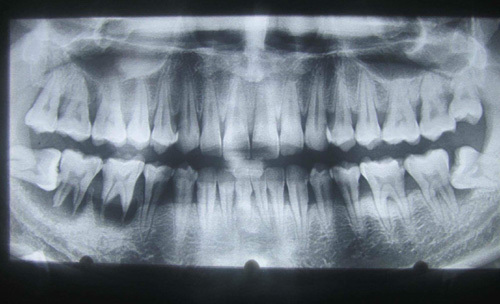

Hình ảnh chiếc răng được nhổ ra từ mũi phải của chị H. |

Tại đây, các sĩ đã chỉ định cho bệnh nhân chụp X-quang. Hình ảnh chụp X-quang cho thấy có một chiếc răng trong mũi của bệnh nhân khiến chị H. vô cùng sửng sốt, bất ngờ. Ngay sau đó, các bác sĩ đã tiến hành nhổ chiếc răng mọc "lạc chỗ" này cho chị H.

BSCKI.Trần Văn Tuy, Trưởng khoa Tai Mũi Họng cho biết: Chiếc răng màu trắng trong khoang mũi phải của bệnh nhân dài khoảng 1cm. Đây là một chiếc răng thừa gây chà xát ở khoang mũi khiến bệnh nhân khó thở. Đặc biệt chiếc răng nằm trong mũi lâu ngày khiến cho bệnh nhân thở có mùi hôi rất khó chịu kèm theo dịch viêm chảy ra nhiều.